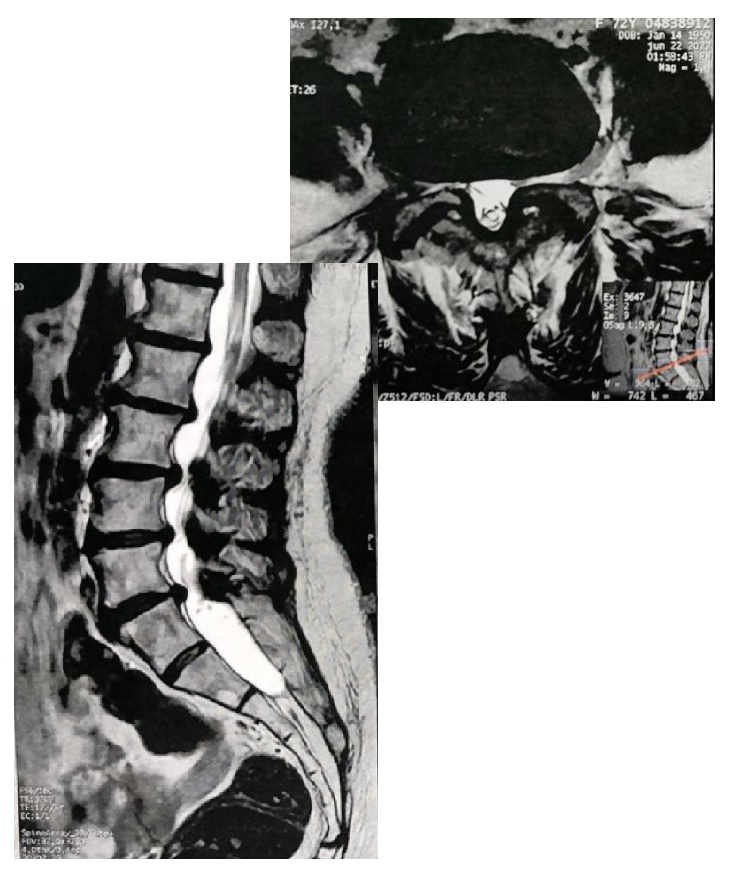

O diagnóstico começa com uma boa conversa (história clínica) e exame neurológico: avalio marcha, força muscular, reflexos, sensibilidade e testes provocativos. Em seguida, a ressonância magnética (RM) lombar é o exame de escolha, pois mostra tecidos moles, compressão nervosa e o grau de estreitamento.

Na RM axial T2, a classificação de Schizas (proposta por Schizas et al. em 2010) é uma ferramenta qualitativa simples e reprodutível para avaliar a morfologia do saco dural (onde ficam as raízes nervosas e o líquido cefalorraquidiano – LCR). Ela divide em 7 graus:

Grau A (estenose ausente ou mínima): LCR visível, raízes ocupam menos da metade do saco (subdividido em A1 a A4 conforme distribuição das raízes).

Grau B (moderada): Raízes ocupam todo o saco, ainda individualizáveis, mas com pouco LCR.

Grau C (grave): Nenhum LCR visível, raízes não reconhecíveis individualmente, mas gordura epidural posterior presente.

Grau D (extrema): Sem LCR nem gordura epidural posterior; saco dural aparece homogêneo e escuro.

Estudos de validação (como Ko et al., PLOS ONE 2020) mostram boa concordância inter e intraobservador, especialmente entre especialistas em coluna. Graus C e D indicam compressão mais severa e maior chance de necessidade cirúrgica.

Imagem ilustrativa da classificação de Schizas (adaptadas da publicação original):

Essas figuras mostram cortes axiais de RM e esquemas: note como o LCR (branco) diminui e as raízes (pontos escuros) se agrupam com o aumento do grau.